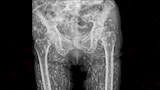

وأثناء الفحص، أجرى الطبيب أشعة سينية كشفت عن وجود مئات الأكياس الطفيلية لمخلوقات غريبة داخل جسم الرجل، نتيجة تناوله لحمًا غير مطهو جيدًا، حسبما ذكرت "ديلي ميل".

ونشر الدكتور سام غالي، طبيب الرعاية العاجلة في فلوريدا، صورة الأشعة على وسائل التواصل الاجتماعي، واصفًا الحالة بأنها واحدة من "أغرب الحالات" التي شاهدها.

وأوضح "غالي" أن البيض الطفيلي الذي دخل جسم المريض عبر اللحم الملوث تحول إلى يرقات شكلت أكياسًا منتشرة في الأنسجة الرخوة بجسمه، خاصة الوركين والساقين.

وأشار إلى أن المريض لم يكن على علم بحالته، وأُجريت له الأشعة بعد تعرضه لسقوط أدى إلى آلام في الورك.